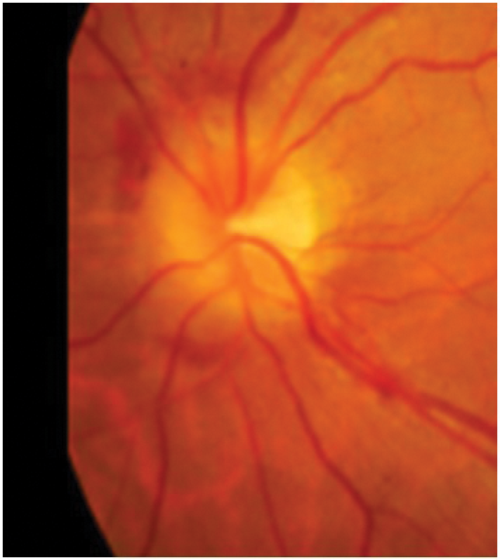

Figure 1: Optic disc photograph showing earliest stage of papilloedema

with swelling of axons at the lower and upper margins.

The clinical appearance of the optic disc in papilloedema must conform with the progressive changes noted in the last paragraph, so that the first part of the disc to show swelling must be where the nerve axons from the retina are most numerous, that is at the upper and lower poles. Here the fibres from the temporal retina arching around the papillomacular bundle enter the limited space at the six and 12 o’clock positions, limited because the nasal retinal axons are occupying a large portion of the nasal portion of the disc and the papillomacular bundle the temporal portion. Thus the place to look for early papilloedema is at the upper and lower poles (Figure 1) and not, as stated in many textbooks, on the nasal side nor in the cup or blood vessels which will only be involved later. As papilloedema progresses all the margins and the disc itself will become swollen (Figure 2), then vascular dilatation becomes evident (Figure 3) leading to leakage of fluid (oedema) and later again haemorrhages appear (Figure 4).